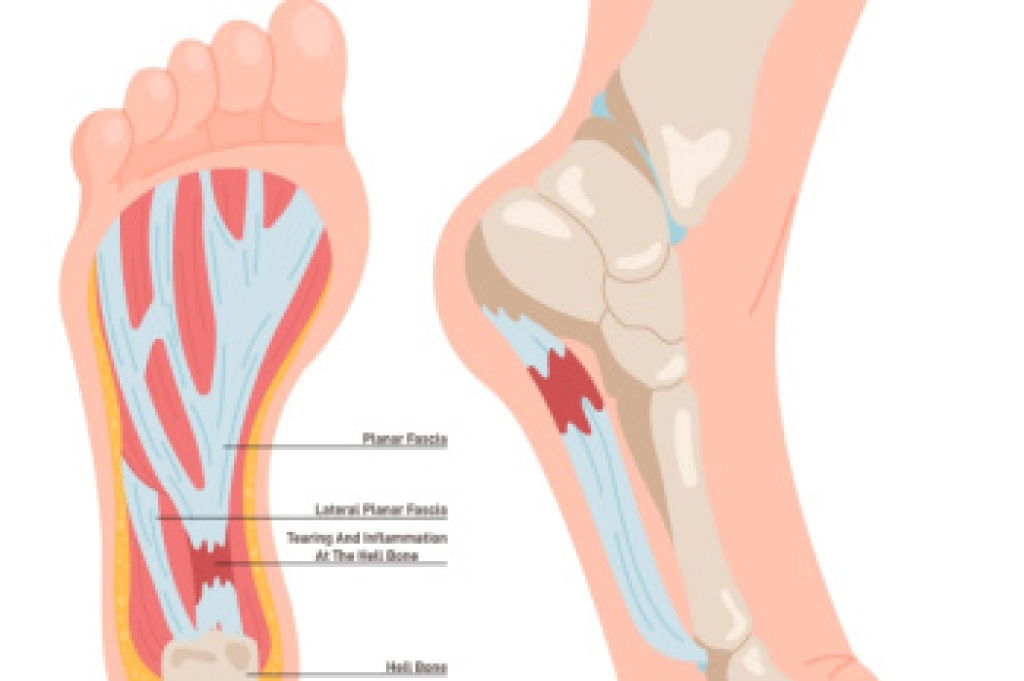

Gout is an inflammatory arthritis caused by the buildup of uric acid crystals within the joints, leading to intense inflammation and discomfort. Symptoms often appear suddenly, and may include swelling, redness, warmth, and severe pain that frequently affects the big toe, but can involve other joints of the foot and ankle. These attacks may occur without warning and can limit walking and daily activity. Causes include elevated uric acid levels in the blood, which may be influenced by diet, genetics, and certain medical conditions. Risk factors include obesity, family history, medications, and metabolic disorders. A podiatrist can diagnose gout through a clinical evaluation, manage painful flare-ups, and develop a treatment plan to protect joint health. If you have symptoms of gout, it is strongly suggested that you are under the care of a podiatrist who can offer you effective relief and management techniques.

Gout is a form of arthritis that is characterized by sudden, severe attacks of pain, redness, and tenderness in the joints. The condition usually affects the joint at the base of the big toe. A gout attack can occur at any random time, such as the middle of the night while you are asleep.